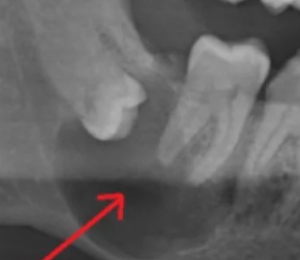

2) 매복 사랑니에 물혹이 생긴 경우

상기 사진처럼 사랑니가 턱뼈에 매복되어 있고 동그랗게 물혹을 만든 경우, 발치가 매우 필요합니다. 처음에는 물혹이 작다가 사이즈가 점점 커지면서 주변 치아에까지 퍼지고 턱뼈 안의 신경을 누르는 경우도 생기기 때문에 매복 사랑니는 되도록 발치를 하시는게 좋습니다.

만약 현재 통증도 없고 엑스레이상 문제가 없는 상태로, 발치가 부담스럽다면 주기적으로 정기 검진을 하셔야 합니다. 정기 검진 시 물혹이 생겼다거나 점점 커지는 것 같다고 하면 그때는 발치를 꼭 하셔야 합니다.